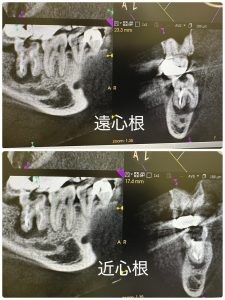

本日、上開始、予想に反してあと3ミリが届かないが

異所だと困るから、試摘CT、ハイ大丈夫👌

3次元的に湾曲形態は頭に入ってるから🤪